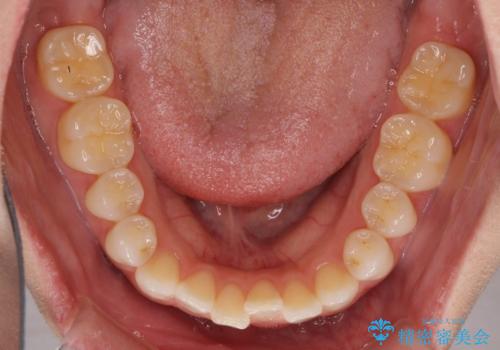

前歯のオープンバイトを治したい インビザラインでの矯正治療

- 前歯の上下スペースによる話しにくさと顎への負担を気にして来院された患者様です。

インビザラインにより上顎の大臼歯を圧下し、上下の前歯の隙間を閉じていくこととしました。

上顎の奥歯を圧下させることで、上下前歯を接触させるように計画しました。

前歯が急に接触するようになり、慣れるまで時間がかかりましたが、前歯でものが咬めるようにもなり、患者様には大変満足していただきました。